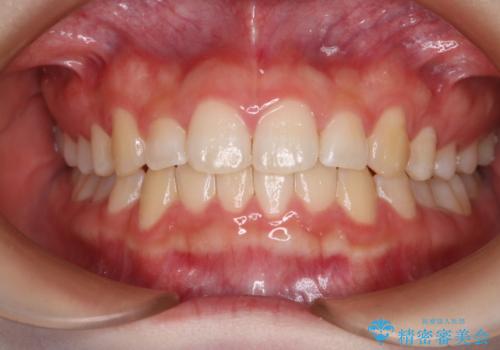

- 前歯のガタつきの改善を主訴に来院された患者様です。

ガタつきによる上顎正中の空隙や歯の突出感も気にされていました。

費用を抑えたいとの事だったので歯の移動量なども考慮し、インビザライン・ライトパッケージでの治療を計画しました。

インビザライン・ライトパッケージでは歯の移動量が限られている分、費用と期間を抑えて治療することが出来ます。